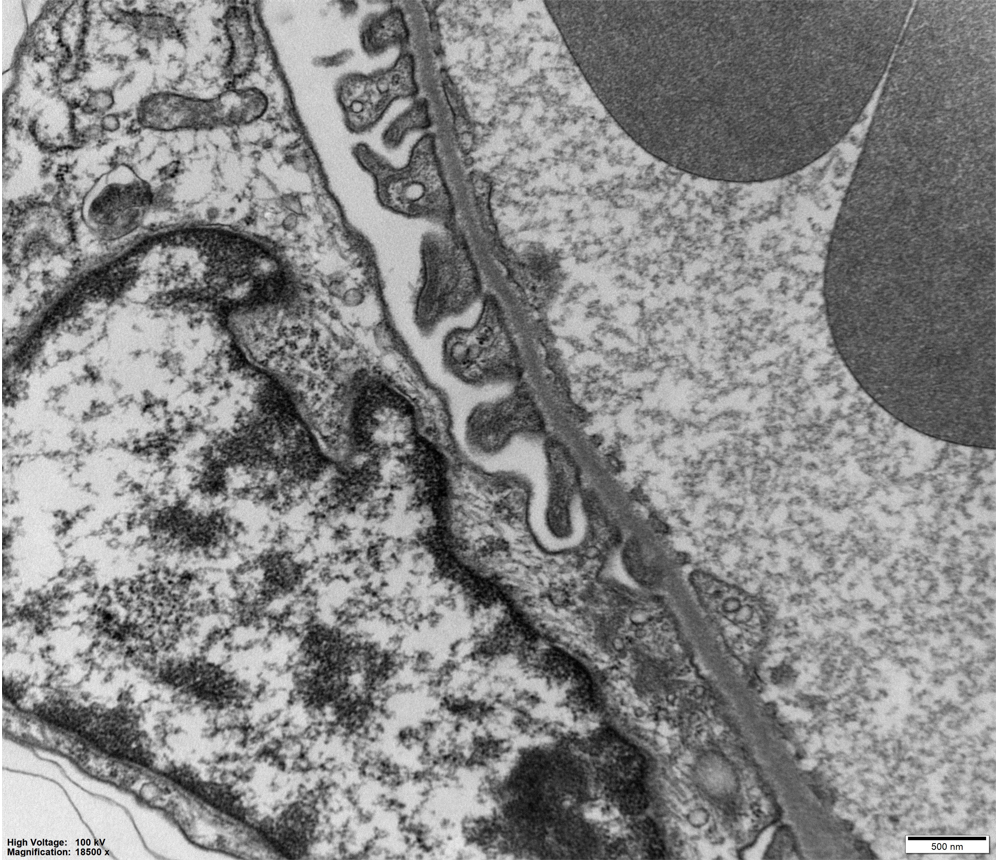

生物物理所阎锡蕴组肾小球足细胞基底膜